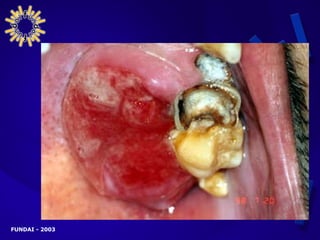

MANIFESTACIONES CLÍNICAS AVANZADAS PRESENTACIÓN DIGESTIVA Lesiones orales Disfagia Dolor retroesternal Dolor epigástrico Nauseas y /o vómitos Dolor abdominal difuso Melena Diarreas Enterorragia Dolor perianal Pujos y Tenesmos